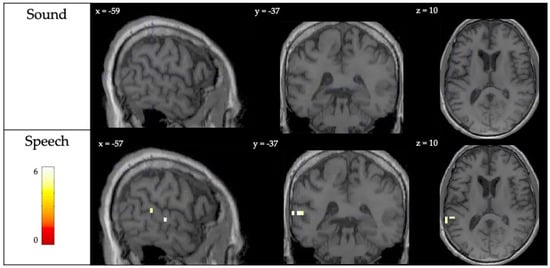

3.1. Auditory Perception

| Sound Perception | Left posterior superior temporal gyrus | −59, −30, 5 | 70 | 5.69 |

| Left superior temporal gyrus | −56, −37, 5 | 5.35 | ||

| Right primary auditory cortex | 61, −11, 5 | 83 | 9.15 | |

| Speech Perception | Left superior temporal gyrus | −67, −48, 10 | 260 | 11.42 |

| Left primary auditory cortex | −56, −37, 5 | 10.17 | ||

| Right posterior superior temporal gyrus | −50, −33, 5 | 9.11 | ||

| Superior temporal gyrus | 61, −7, 0 | 186 | 9.58 | |

| Right posterior superior temporal gyrus | 57, −22, 0 | 8.72 |

| Speech Perception | Left superior temporal gyrus | −59, −37, 10 | 2 | 5.96 |

| Left superior temporal gyrus | −67, −37, 10 | 3 | 5.37 | |